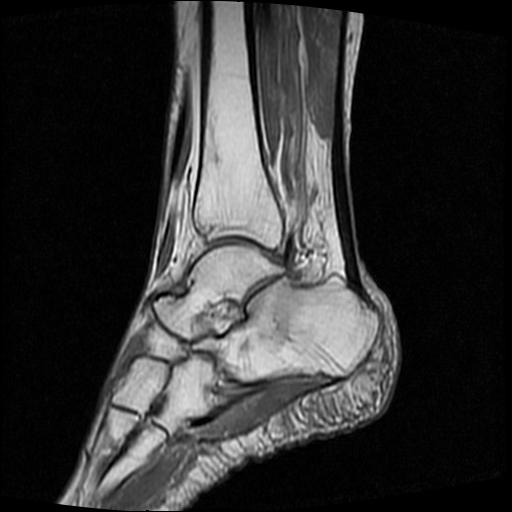

标题: MRI0968:女性,70岁,跟骨信号异常 [打印本页]

标题: MRI0968:女性,70岁,跟骨信号异常

女性,70岁,右侧跟骨疼痛2个月,负重时加剧,不负重时不疼。

胫骨下段,跟骨、距骨可见斑片状异常信号区;考虑:转移瘤

跟骨cr片正常。

跟骨长t1长t2信号异常,边缘模糊(肿瘤一般边界清楚,故肿瘤不考虑),压脂像呈高信号--骨髓水肿(炎症?)。